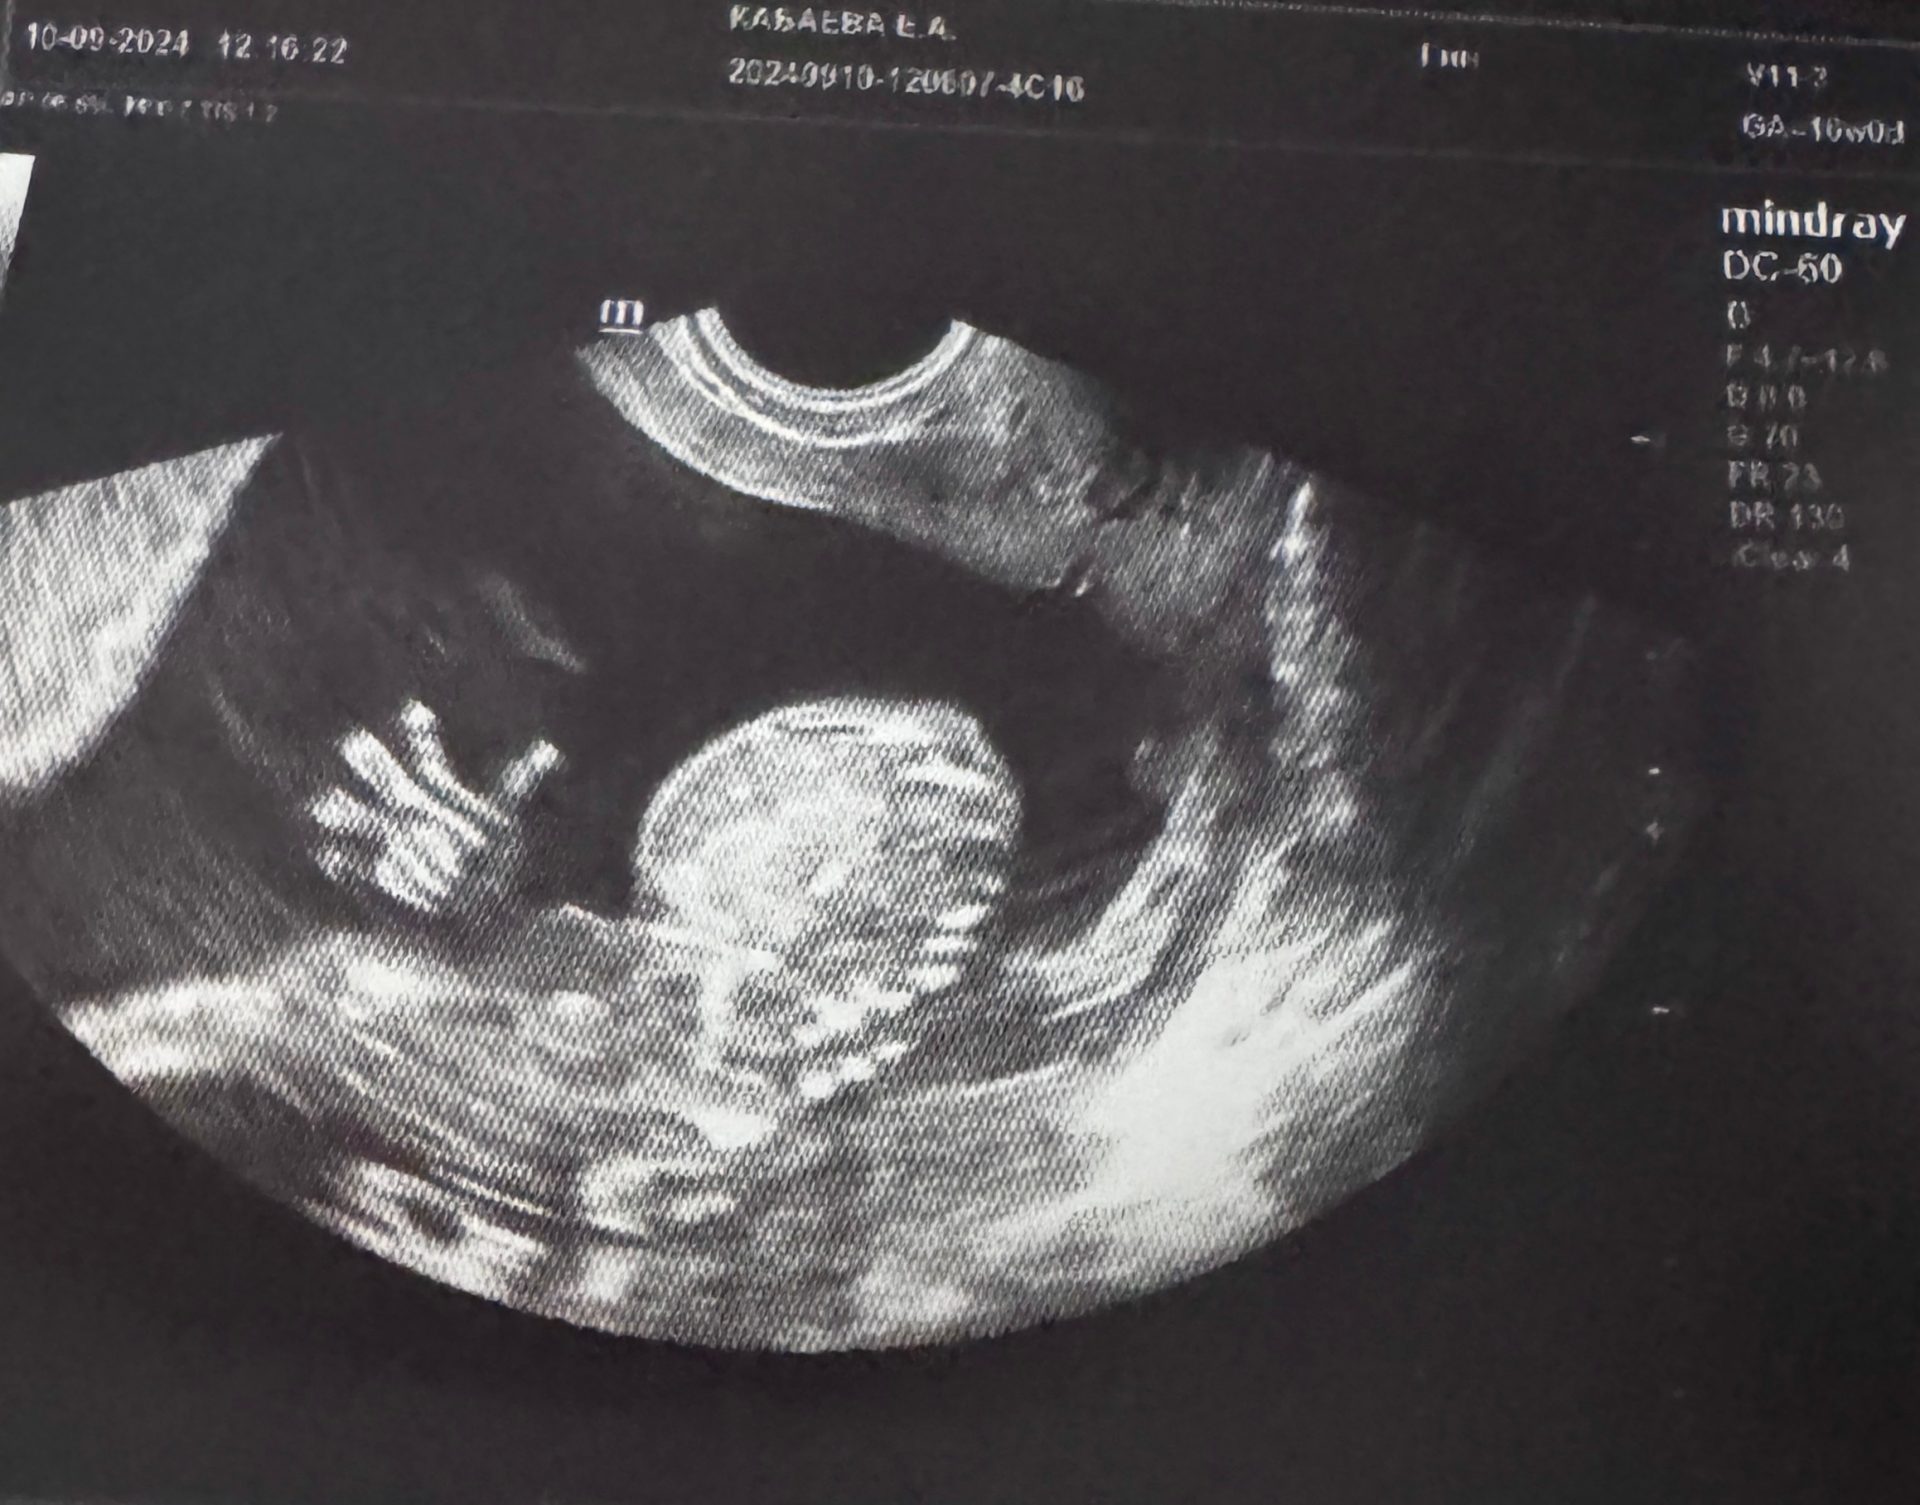

Сегодня мы публикуем историю Елены и Дениса Кабаевых. Начинающие родители, как они сами себя с улыбкой называют, рассказали её на семинаре, посвящённом запуску программы Клинической больницы №50 «Мама в ЗАТО». И не будет преувеличением сказать, что у всех участников мероприятия на глазах выступили слёзы от восхищения этой прекрасной парой и их малышом.

«Наше чудо по имени Даня случилось благодаря врачам Клинической больницы №50. Это была моя третья беременность… И первый ребёнок. Две предыдущие, такие желанные, я потеряла: одну — на 21-й неделе, вторую — на 9-й. Принять это оказалось невероятно тяжело. Перед новой попыткой мы с мужем, по совету заведующей акушерским отделением Екатерины Шевцовой и заведующей женской консультацией Елены Иосилевич, прошли все возможные обследования. Выяснилось, что всё в порядке, ЭКО не нужно, а нужно… В отпуск! Сразу после моря я уехала на чемпионат AtomSkills и, вернувшись домой, увидела две заветные полоски», — вспоминает Елена.